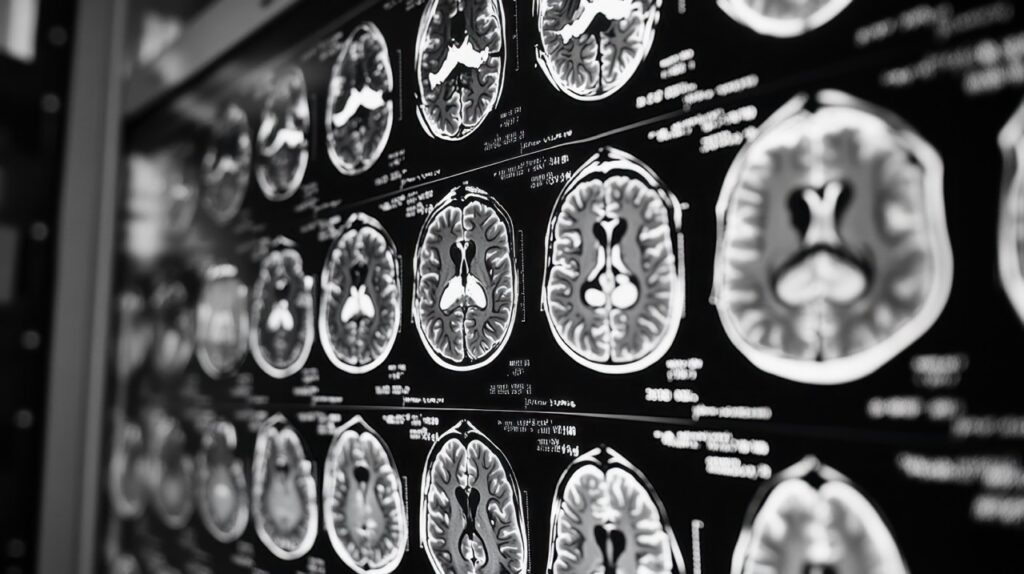

How MRI Helps Prevent Long-Term Sports Injuries

MRI for Sports Injuries: Detect Problems Early and Prevent Long-Term Damage Athletes often push through minor pain, thinking injuries will heal on their own. Unfortunately, small problems can become major complications when left untreated or undiagnosed properly. A sports injury MRI identifies hidden damage before it worsens into chronic conditions. Early detection through sports injury […]

Diagnostic Imaging in Sports Medicine: The Crucial Role of MRI

Sports Medicine MRI: Essential Imaging for Injury Diagnosis Sports injuries can sideline athletes at any level of competition. Professional players, college athletes, and weekend joggers all face the same challenge when injury strikes. One day you’re running freely, and the next day every step brings pain. Getting back to your sport requires an accurate diagnosis […]